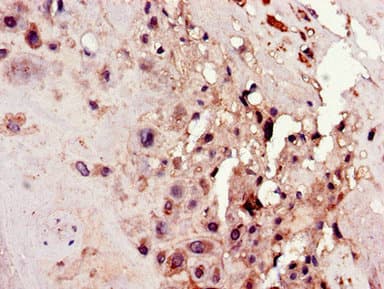

Anti-C4orf26 antibody(ab223071)

Rabbit Polyclonal C4orf26 antibody. Suitable for IHC-P and reacts with Human samples. Cited in 1 publication. Immunogen corresponding to Recombinant Fragment Protein within Human Odontogenesis associated phosphoprotein aa 1 to C-terminus.

Applications IHC-P

Species Reactivity Human